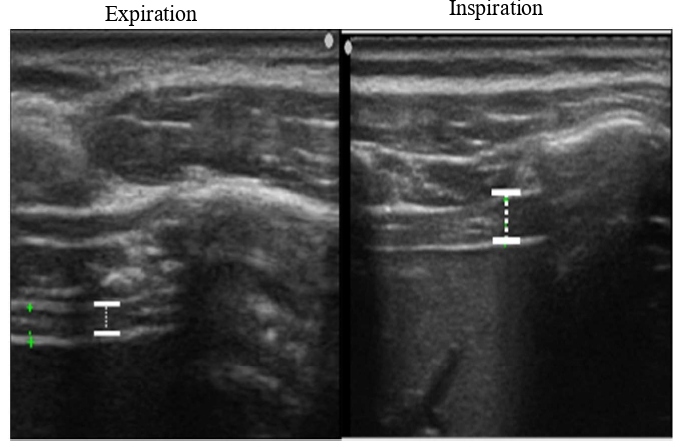

We imaged the distance of diaphragmatic movement (Ddi) and the thickness of the diaphragm (Tdi) using US (7.5 MHz linear probe, Ultrasound System ARIETTA Prologue, B-mode, Hitachi, Japan). The right side of the sites for measuring Ddi and Tdi was set as the region of interest because the left diaphragm is difficult to visualize given the presence of gastrointestinal organs [13-18]. The Ddi was imaged on the right mid-axillary line from the 9th–10th intercostal space to the upper border of the zone of apposition (ZOA) between the midclavicular line and the anterior axillary line. Ddi was defined and measured as the change in the distance from any ribs in the visual field to the diaphragm [14,17,18]. Tdi was imaged at the ZOA on the mid-axillary line. According to the method by Wakai et al.[16], muscle thickness was imaged at the same site, and the difference in the muscle thickness between the end of inspiration and end of expiration was defined as the difference in the Tdi, which was used as an index of the amount of diaphragm activity (Figures 1 and 2).

Figure 2: Thickness of the diaphragm (Tdi) in US. TDi: Thickness of the Diaphragm; US: Ultrasonography.

In the image analyses [17,18], the following indices of respiratory muscle activity were calculated using the obtained images and an image-analyzing software (Image J®). The ratio of Ddi to height (Ddi/Ht) was also calculated using the following formula: Ddi/Ht (%) = Ddi (cm)/height (cm) × 100. The maximal muscle thickness was measured as Tdi during QB and FAB.